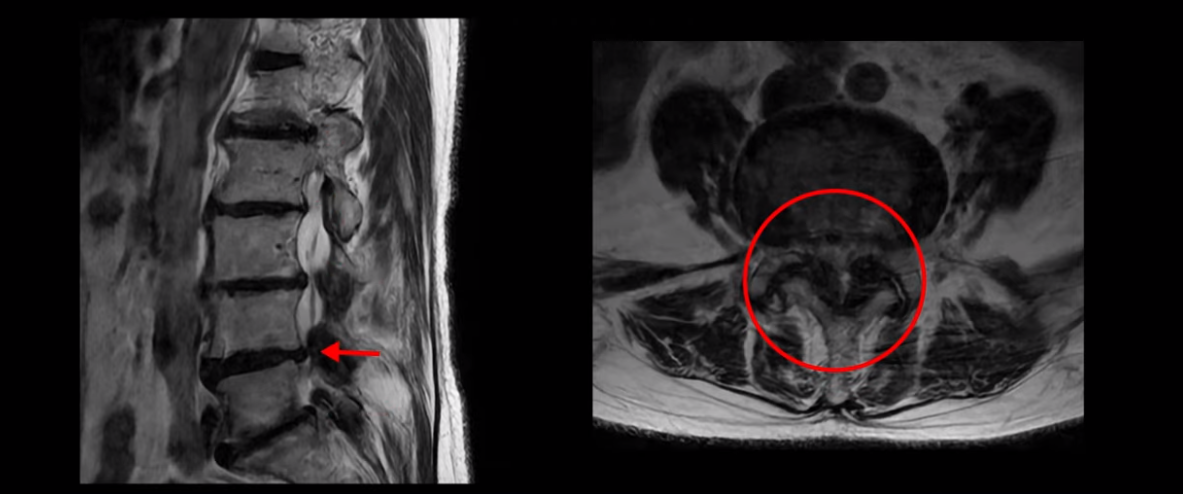

이분 MRI를 보고 설명해 드린 후 어떻게 허리 여러 마디에서 신경이 심하게 눌려 보이는 협착증 환자가 수술 없이 좋아질 수 있는지, 또 치료는 어떻게 하는지 설명해 드리겠습니다.

이분 MRI 보시다시피 허리 다섯 마디가 전부 다 퇴행이 심합니다.

특히 4번 5번에는 심한 중심성 협착이 있고,

5번 1번에는 황색인대가 골화되어 왼쪽 신경 나가는 길이 좁아져 있습니다.

그래서 왼쪽 엉덩이와 다리 통증이 더 심합니다. 이렇게 신경 구멍들이 좁아져 있고 신경이 눌리니까 엉덩이와 다리가 너무 저리고 아프고 힘도 빠져서 몇 걸음도 걷기 어려우니까 지팡이를 짚고 저녁에도 아파서 잠을 못 자는 겁니다.